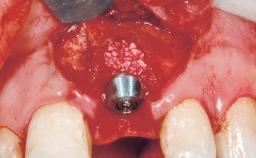

Immediate Placement of an Implant in a Maxillary Right Central Incisor Site

A 30-year-old female patient was referred to the office for the treatment of tooth 11. Her chief concern at the initial visit was to inquire, “Why is my tooth pink?” Upon clinical examination, it was determined that tooth 11 had a previous history of trauma and that the clinical crown had become noticeably pink in color as a result of internal resorption. This diagnosis was confirmed radiographically, indicating a large radiolucency involving the central and distal portions of the clinical crown. It was determined that restoration of this tooth was not possible, and that extraction was indicated. The presence of a mid-line diastema, which the patient wanted to reproduce, directed the treatment plan for tooth replacement utilizing a dental implant.

| Placement Protocol | Immediate implant placement |

| Tooth Site | Maxillary incisor or canine |

| Socket Morphology | Single-root socket |

| Socket Integrity | Sufficient, with intact bone walls |